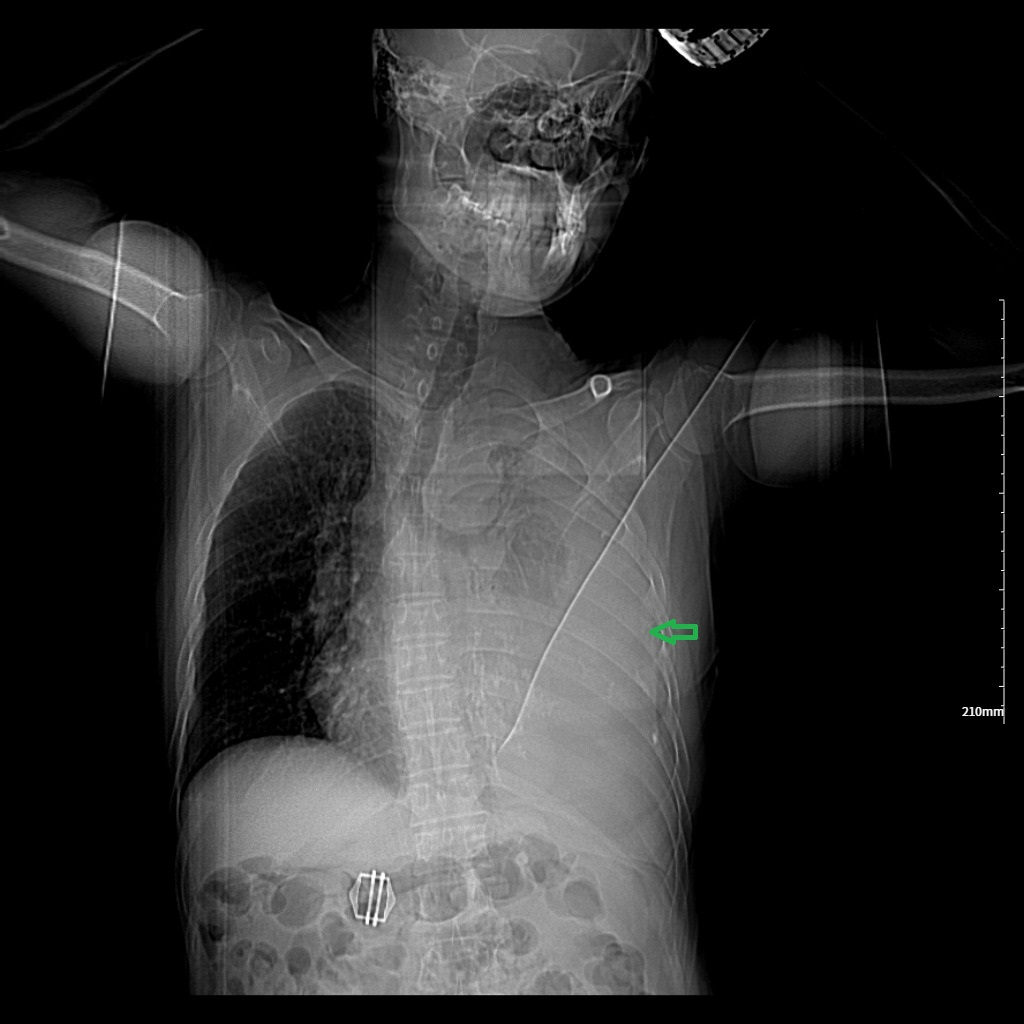

胸部CT示两肺及肋骨平扫未见明显挫伤征象,左侧胸腔包裹性积液并胸膜增厚、钙化,左肺不张(见图1-图4)。

1. 绿色箭头:左侧大量胸腔积液。